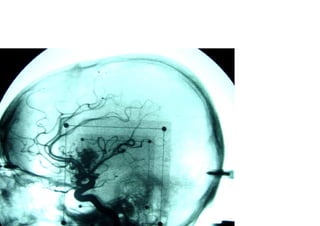

Vascular

Hemorragica

Isquemica